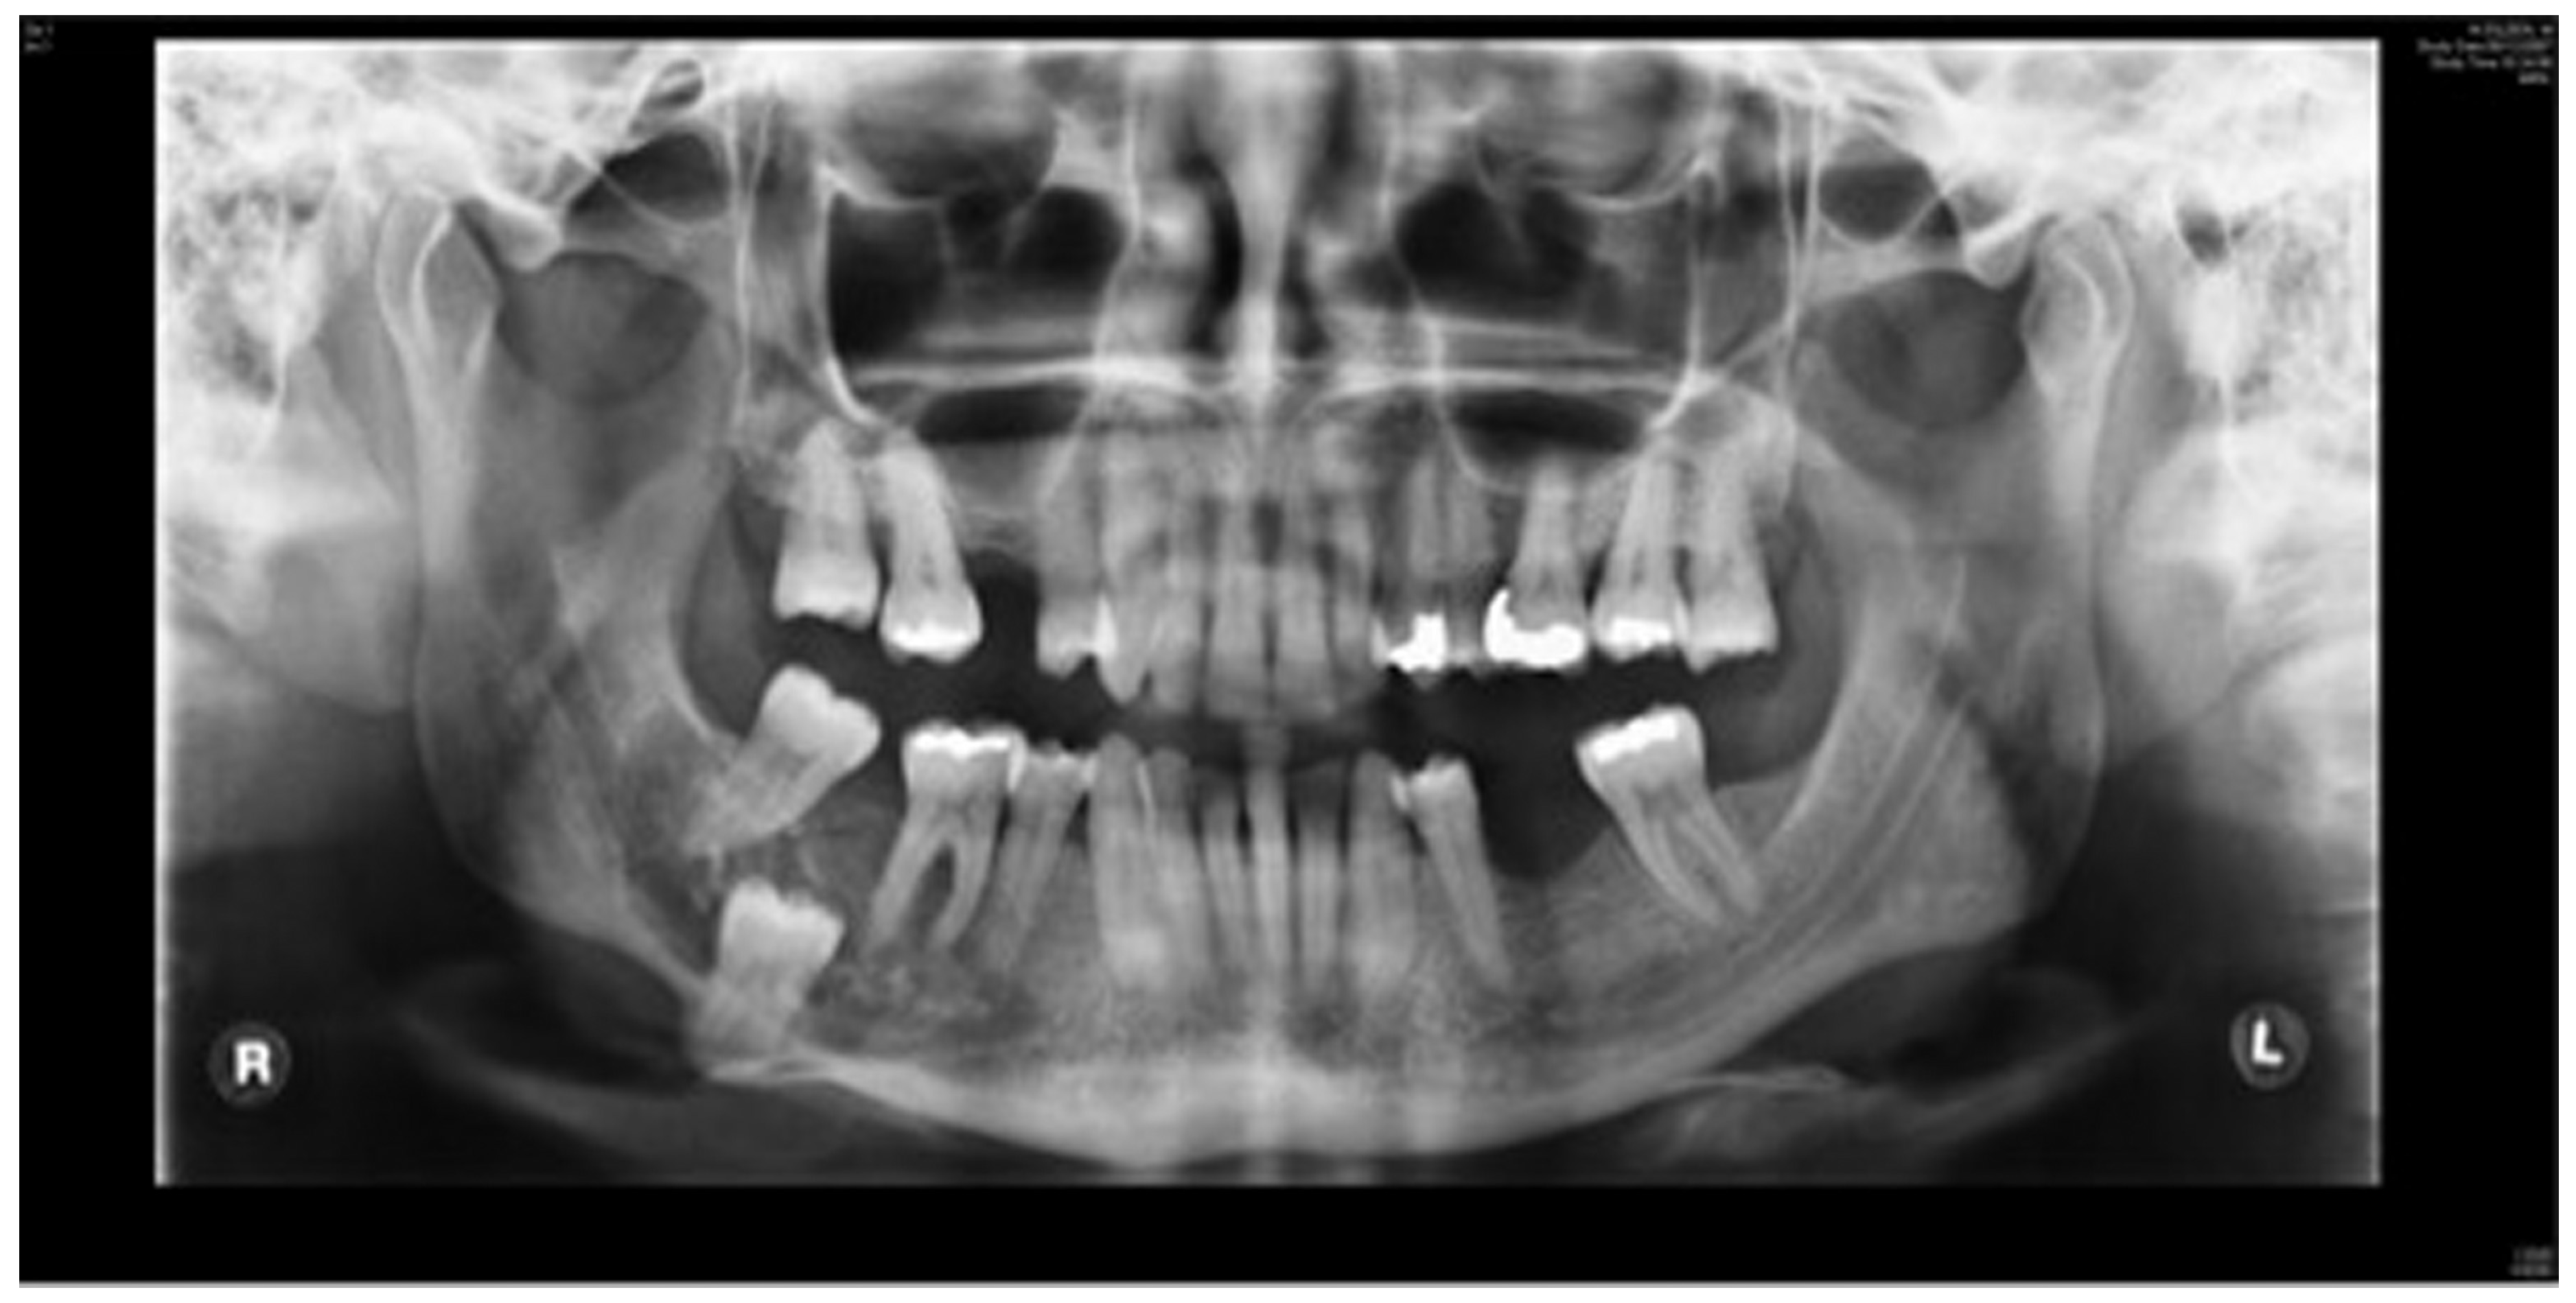

Figure 10.

Stage 1 surgery. Orthopantomography (OPT) to show locking plate to maintain the position of bony fragments whilst oral mucosa is healing in gun shot wound case.